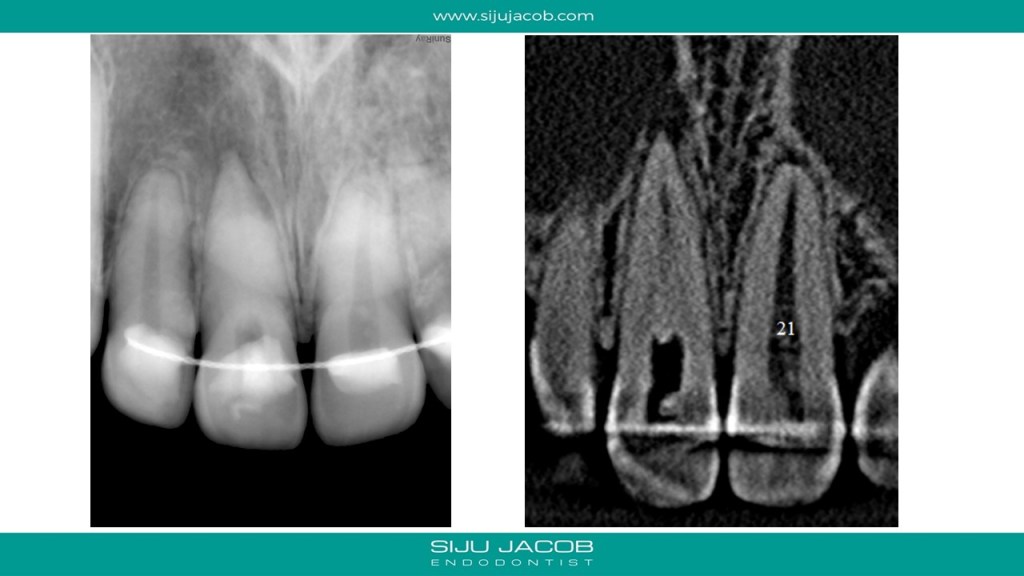

This case was calcified all the way to the apical one third. As we go deeper, the labio-palatal orientation becomes a problem and as we approach the apical part, the margin for error decreases. In this case, I took an inter-appointment CBCT to see the location of the canal. The video explains the whole process.

And here are the pics for the case: